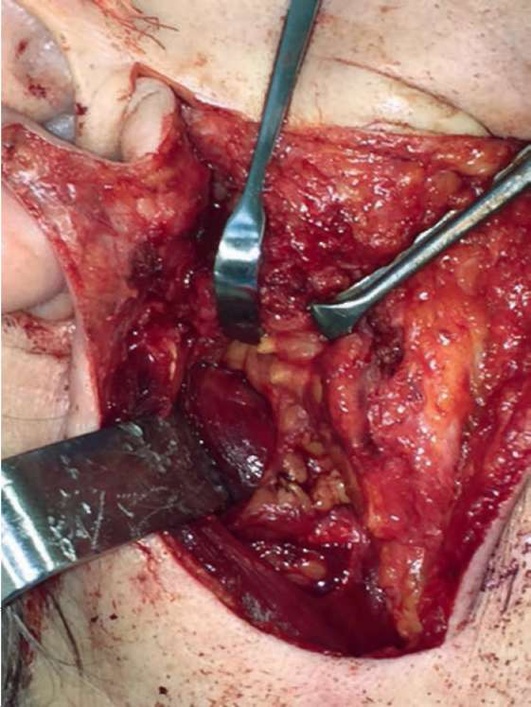

Лечение пациентов слюннокаменной болезнью заключается в удалении конкремента и создании условий, предотвращающих рецидив камнеобразования. Если камень располагается в околоушном или под-нижнечелюстном протоках либо в околоушной железе, то его удаляют. Если камень локализуется в под-нижнечелюстной железе, то его удаляют вместе с железой.

В настоящее время разработаны органосохраняющие операции, при которых в случае расположения камня в поднижнечелюстной железе удаляют конкремент, оставляя слюнную железу (В.В. Афанасьев, М.Р. Абдусаламов).

Удаление камней из поднижнечелюстного и околоушного протоков проводят в амбулаторных условиях. Удаление камней из внутрижелезистых отделов околоушного протока и экстирпацию поднижнечелюстной слюнной железы производят в условиях стационара. Для предупреждения рецидива камнеобразования В.В. Афанасьев рекомендовал проводить операцию по созданию нового устья протока.